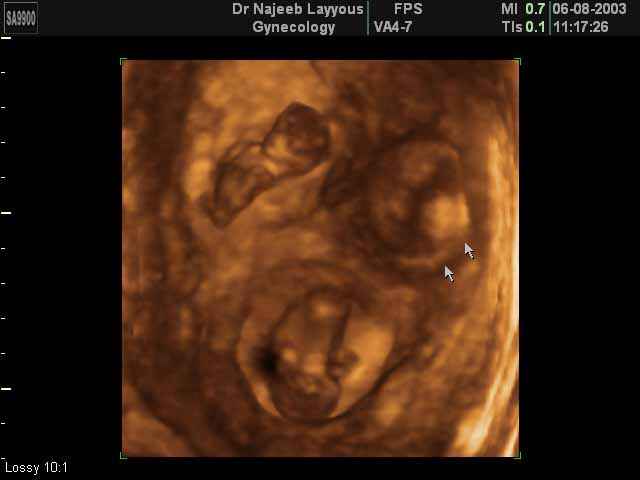

- صور لتوائم